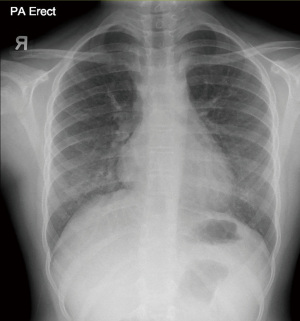

At outpatient follow up, she remained symptom-free. Oxygen was stopped by six weeks post discharge with good overnight pulse oximetry profile in room air. With rehabilitation, she was gradually able to return to school and participate in physical activities. At nine months post-discharge, CXR still showed fine reticular opacities in bilateral lower zones (Figure 3), while her spirometry remained normal.